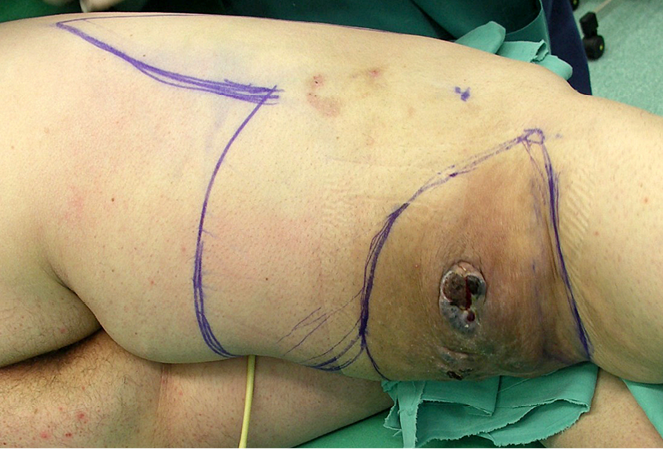

Praėjus kuriam laikui recidyvas pasikartojo naujo rando srityje. Pacientė toliau tirta, dariniui platėjant konsultuota kelių specialistų (žr. 1A pav.). Rekomenduota amputuoti galūnę šlaunikaulio viršutinio trečdalio lygyje, tačiau pacientė pasiūlytą operaciją kategoriškai atmetė.

1A pav. Dešiniojo pakinklio paviršiumi plintančios melanomos recidyvas prieš operaciją

Pasirinkta operacijos taktika: platus darinio pašalinimas sveikų audinių ribose, skubi biopsija auglio plitimui odos ir pašalintų audinių kraštuose nustatyti ir susidariusio defekto padengimas dviskilčiu odos pasukiniu (rotaciniu) lopu (žr. 2A pav.).

2A pav. Prieš operaciją pažymėta preliminari operacinių pjūvių schema